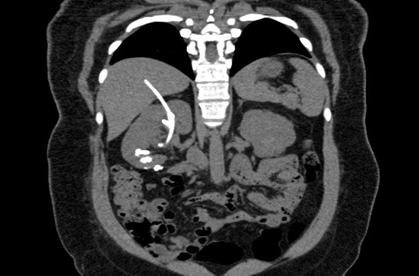

Over the past two years, she experienced worsening right flank pain, initially non-migratory and burning, progressing to colicky pain. She reported gross hematuria (three episodes per month) and was hospitalized for pyelonephritis between 2023 and 2024, requiring prolonged antibiotic therapy. Despite treatment, sporadic colic and hematuria persisted. She was admitted to our service in January 2025. A new abdominal CT confirmed the presence of the forgotten catheter transfixing the liver and entering the right kidney via the superior calyx (Figure 1), along with multiple renal calculi, prompting her hospitalization for surgical intervention (Figure 1).

Figure 1 Preoperative CT image: Right kidney with several calculi and foreign body, which transfixes the liver.